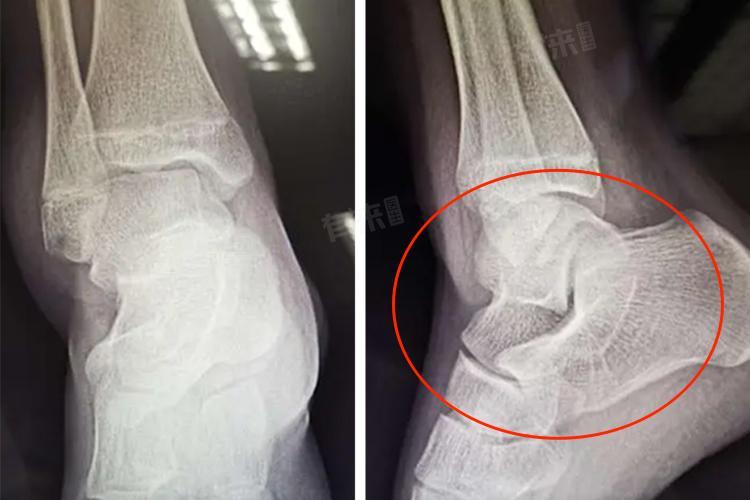

2、检查部位:手腕、脚踝等小部位的普通透视检查,价格较便宜,通常50-100元。头颅、胸骨、髋关节等复杂部位,可能需病灶体层摄影等方式,价格相对昂贵,在200-500元。